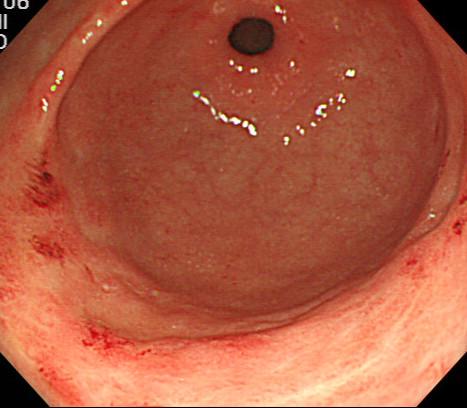

A 47-year-old female patient with advanced renal cell carcinoma was treated with temsirolimus. Eight weeks after starting targeted therapy, the patient was admitted to our hospital for worsened fatigue, pallor, and hematemesis. A complete blood count showed a marked drop in her hemoglobin level from 10.1 g/dl 4 days earlier to 2.9 g/dl. Esophagogastroduodenoscopy revealed diffuse mucosal bleeding of the antrum. Endoscopy revealed diffuse reddish spots that resembled gastric antral vascular ectasia (GAVE) extending from the pylorus into the antrum. One month after endoscopic hemostasis with APC and stopping temsirolimus, significant improvement was shown in the gastric erythema and GAVE like lesions.

一名 47 岁女性患有晚期肾细胞癌,接受替西罗莫司治疗。靶向治疗开始 8 周后,患者因疲劳、苍白和呕血入住我院。全血细胞计数显示其血红蛋白水平从 4 天前的 10.1 g/dl 明显下降至 2.9 g/dl。食管胃十二指肠镜检查显示胃窦弥漫性黏膜出血。内镜检查显示弥漫性红色斑点,类似于从幽门延伸至胃窦的胃窦血管扩张症(GAVE)。APC 内镜止血并停用替西罗莫司 1 个月后,胃红斑和 GAVE 样病变明显改善。